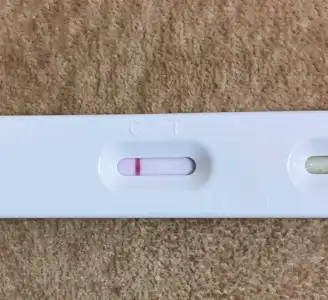

Hahahhaha öteki tarafa gel atcam ben sana test 5 gün sonraCanım test çekti test aşeriyorum. Bide bu ay umduğumdan erken geldi adet hiççç yapamadım canım sıkılıyor ellerim titriyor. Abla bana bir test ya noooollllluuuuurrr abla yaaa